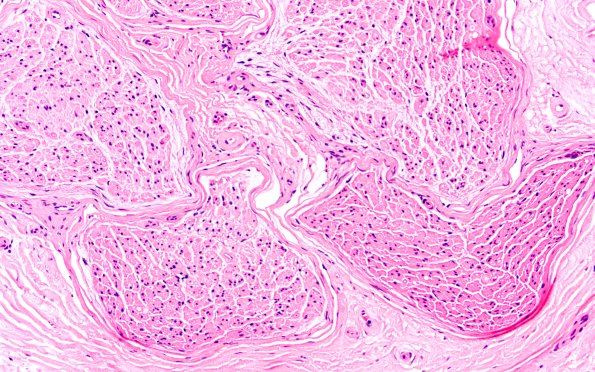

6C3 Crush artifact 20X 1

6C3,4 Higher magnification images of image #6C2. (H&E)